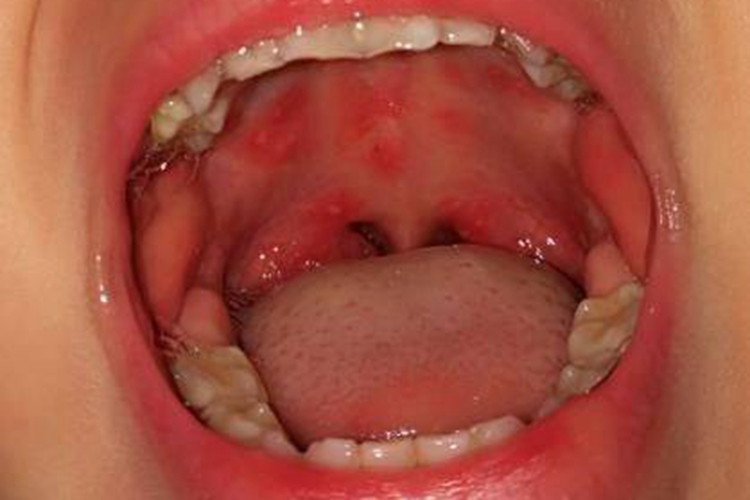

手足口病多见于2-10岁的儿童,潜伏期3-7天,发疹前可有不同程度的低热、头痛、纳差等前驱症状,1-3天后手、足、口部出现皮损,初期为红色斑疹,很快发展为2-4mm大小的水疱,疱壁薄,疱液清亮,周围绕以红晕,水疱溃破后可形成灰白色糜烂面或浅溃疡。手足口病一般不会出现瘙痒的症状,可能会伴有轻微疼痛。

手足口病初期以对症、支持治疗为主。口腔损害可用口腔溃疡涂膜剂或利多卡因漱口等以减轻疼痛;皮损处可外用炉甘石洗剂。板蓝根颗粒内服有一定效果,也可选用抗病毒药物,如利巴韦林等。